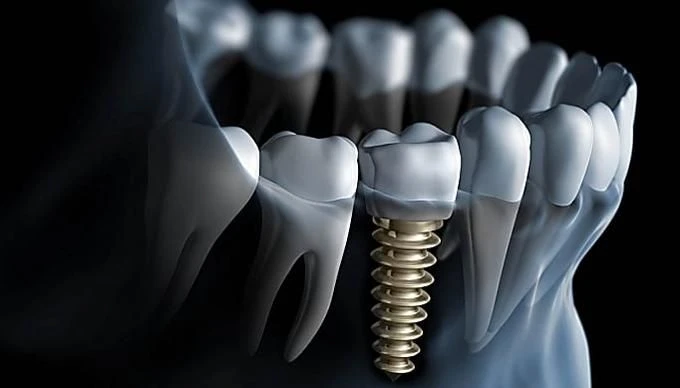

Tomografi genellikle, bir dişin kökünde bir enfeksiyon ya da kist olup olmadığını veya diş implantı yerleştirmeden önce kemik yapısının uygun olup olmadığını belirlemek için kullanılır. Ayrıca, diş çürüğü ve diş eti hastalıkları gibi diş problemlerinin teşhisinde de yardımcı olabilir.